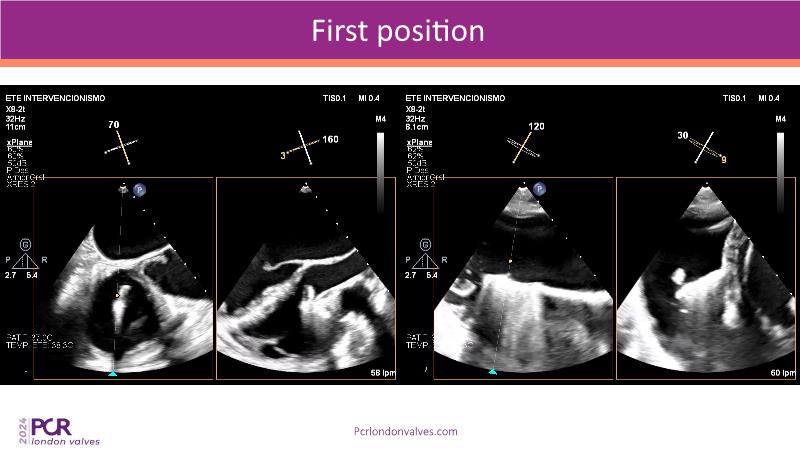

This session examines two compelling cases: a 78-year-old woman with paroxysmal atrial fibrillation, chest trauma, an osteoporotic sternum fracture, and NYHA II exertional dyspnoea, and an 82-year-old man with chronic three-vessel coronary artery disease, bradycardic AF, peripheral arterial disease, spinal stenosis, and chronic kidney disease. Through their study, discover the intricate anatomy of atrioventricular valves, the therapeutic challenges they pose, and the growing significance of transcatheter edge-to-edge repair (TEER) therapies. The discussion also highlights the value of multidisciplinary strategies in managing complex valve diseases effectively.